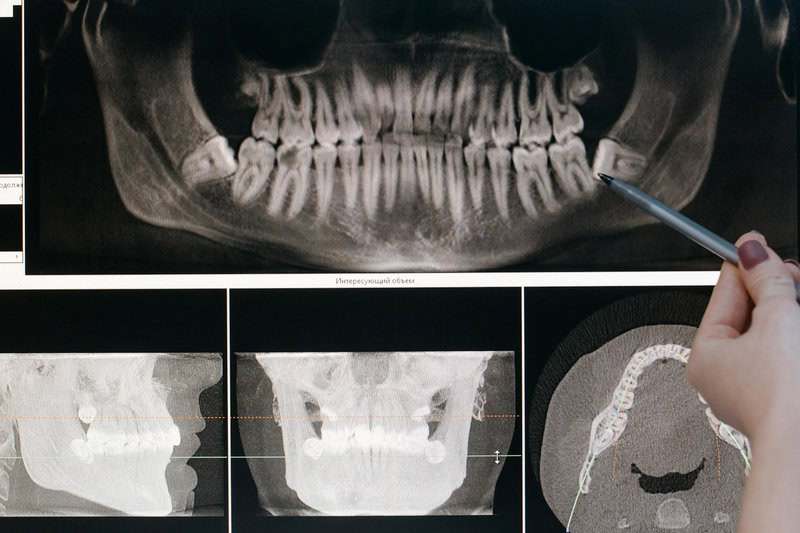

3. X-rays by Wilhelm Röntgen

A Crookes tube apparatus used by Wilhelm Röntgen to discover X-rays from cathode ray experiments. | Photo by cottonbro studio on Pexels

In 1895, German physicist Wilhelm Röntgen was investigating cathode rays when he noticed a fluorescent screen glowing unexpectedly. This led to the discovery of X-rays, a form of radiation that could pass through solid objects and reveal their internal structures. Röntgen’s first X-ray image depicted the bones and wedding ring of his wife’s hand, marking a pivotal moment in medical diagnostics. For more details, visit Britannica.